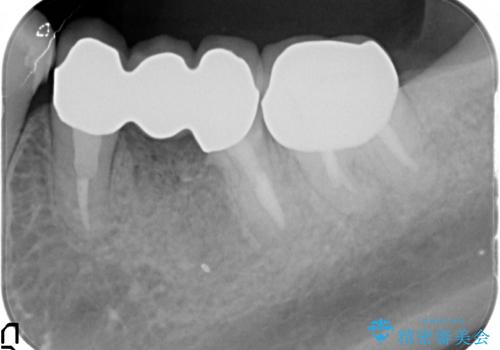

X線写真・視診より歯の破折クラウン下の虫歯再発が認められます。

クラウンの除去・虫歯の除去、根管治療を行ったのち、上顎は強い咬合力に対し破折抵抗性のある咬合面をメタルにしたメタルボンドによる補綴を計画します。